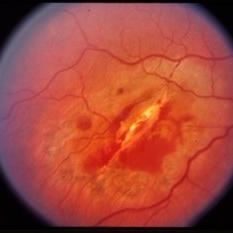

Pre-retinal and retinal hemorrhage.

Condition/keywords: retinal hemorrhage, trauma